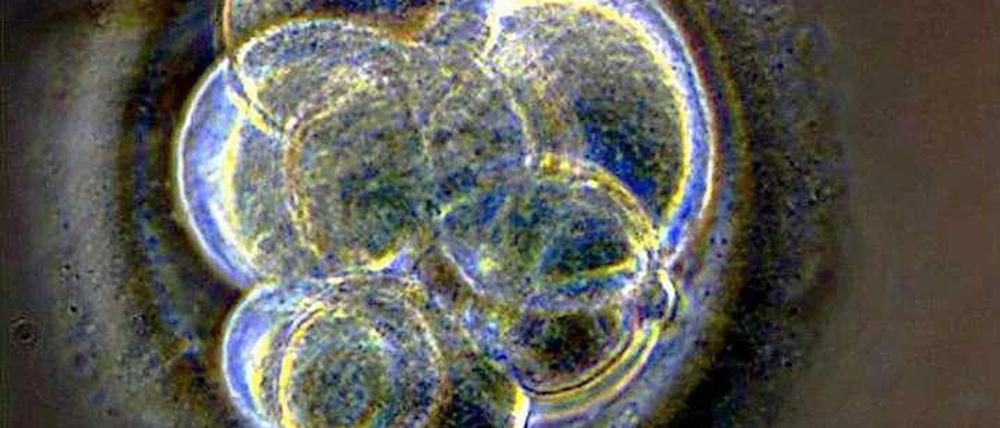

Wenn dem frühen Stadium eines Embryos, der aufgrund eines Gendefekts keine Niere bilden kann, genetisch intakte Stammzellen untergeschoben werden, dann können die Stammzellen dieses Organ bilden. So könnten in Tieren Organe aus menschlichen Zellen gezüchtet werden.

Schon vor einiger Zeit haben Forscher eine vielversprechende Methode entwickelt, um menschliche Organe wachsen lassen. Dazu spritzen sie Stammzellen in frühe Stadien von Rattenembryonen, die aufgrund bestimmter Genmutationen nicht in der Lage sind, ein bestimmtes Organ wie die Niere selbst zu entwickeln. Diese Aufgabe übernehmen die menschlichen Zellen in dem Mischembryo, so dass in der Ratte ein menschliches Organ heranwächst. Doch je älter diese Organe in dem Tier werden, umso mehr Rattenzellen wandern in das Organ ein, zum Beispiel in Form von Blutgefäßen. Auch der Harnleiter besteht aus einem Gemisch menschlicher und tierischer Zellen.